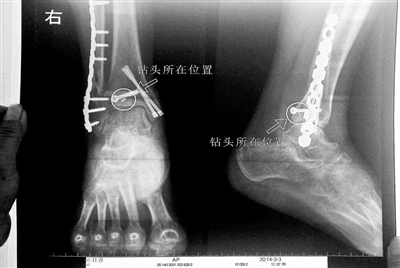

胡女士的腿部X光圖

近日,在豐臺區(qū)右安門醫(yī)院,北京青年報記者見到了胡女士,她走起路來顯得一瘸一拐,腿腳并不利索。在她帶來的X光片上,可以清晰地看到,有一個異物存在于腿內(nèi)部。

“我當(dāng)時就嚇蒙了,怎么會有一個鉆頭在骨頭里?”胡女士余悸未消地說,第二天拍攝的X光片顯示,2厘米左右的鉆頭遺留在她右腳腳踝上部的骨頭內(nèi)。

胡女士說,當(dāng)時旁邊的醫(yī)生勸慰自己,稱鉆頭留在腿里并不會有什么問題。出院后,胡女士每個月都會來醫(yī)院做復(fù)查,拍X光片。她說,每次都能夠清晰地看見自己骨頭里的那個明晃晃的“小東西”。